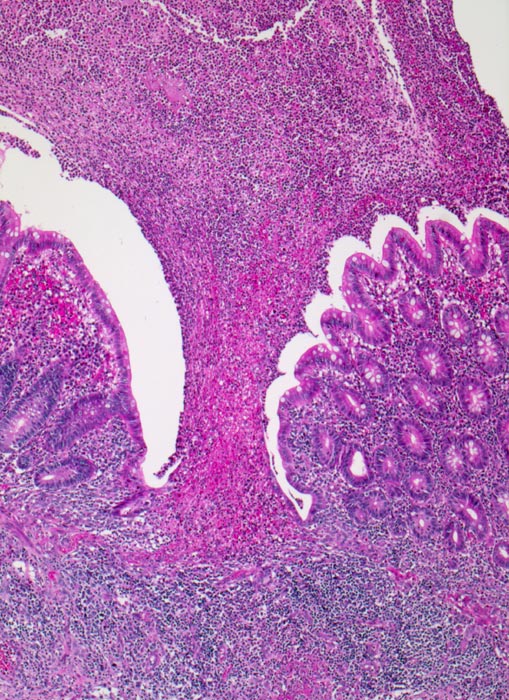

PathoPic ID 3431 - akute eitrige ulzerophlegmonöse Appendizitis: Ulkus

akute eitrige ulzerophlegmonöse Appendizitis: Ulkus

Appendix vermiformis

Oberflächliches Ulkus der Schleimhaut. Appendixlumen gefüllt mit Eiter.

Seit 6 Stunden Schmerzen im Unterbauch rechts mit zunehmender lokaler Druckempfindlichkeit. Übelkeit.

Histologie

25

8

männlich